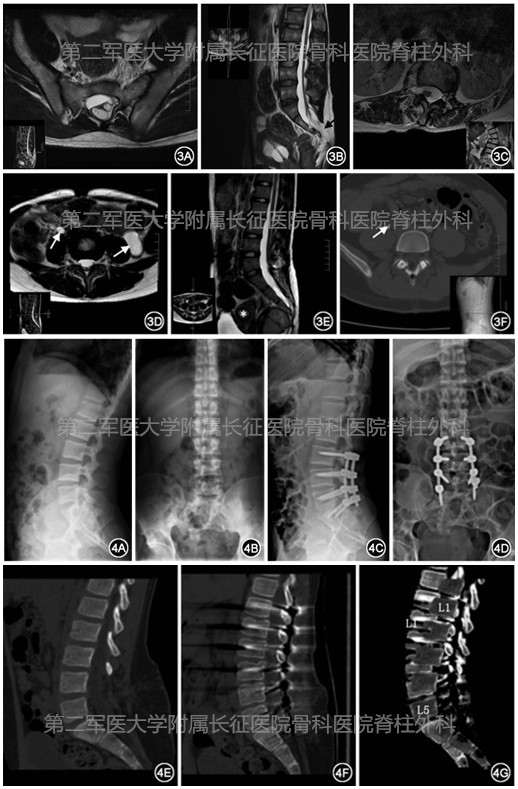

术前15例均有明显的括约肌功能障碍,其中有膀胱功能障碍的9例,其中3例伴肾积水,1例出现肾功能失代偿,存在肠道功能障碍的8例,性功能障碍1例,下肢感觉功能障碍8例,腰痛及下肢疼痛9例,11例为下肢运动功能障碍,3例患者伴单侧足下垂,全部患者的正常生活和学习均受到明显的影响。从首个症状主线计算发病时间中位数及四分位距离为3(1~7)年。15例患者体格检查均表现为下肢病理反射阳性,腱反射减弱。下肢肌电图为外周神经损伤表现(图3 )。

图3 各类TCS患者的影像学表现。A、B:病例6 术前的腰椎MRI平扫水平面和矢状面T2加权相,A:骶椎椎板闭合不全,骶管内脊髓被脂肪组织包裹,B:受到栓系的脊髓在腰段紧贴椎管后壁走形,黑色箭头示骶管内脂肪组织与皮下脂肪相连续;C:病例4 术前的腰椎MRI平扫冠状面T2加权相。图中可见脊髓偏向椎管的凹侧以减轻轴向牵拉;D、E :病例8 术前的腰椎MRI平扫水平面和矢状面TT加权相,D :白色箭头示双侧输尿管扩张,左侧为重,E :受到栓系的脊髓在腰段紧贴椎管后壁走形,盆腔内可见极度扩张的膀胱和肠管,星号标注位置为增厚的子宫内膜;F:病例13 术前的增强腰椎CT水平面动脉相,白色箭头示右侧输尿管扩张,该患者入院前9个月曾在当地医院行“终丝切断椎管减压术”,星号标注的椎板与下关节突之间骨质不连续图4 病例6 手术前(A、B)后(C、D)患者正侧位平片。对患者侧位平片中手术节段内所有椎体的上下终板中点做一连线,各节段相应椎管后缘作一连线,对比术前与术后两连线均值之差即为脊柱缩短长度,该患者脊柱缩短19.4mm。病例11 手术前后CT矢状位重建像。E为术前正中矢状位重建像;F为术后正中矢状位重建像;G为将E、F的骨质部分提取,红色为术前腰椎、绿色为术后腰椎,将手术前后L5椎体重合,对比L1椎体位置,显示术后脊柱短缩长度,该患者短缩长度为20.5mm

患者手术时间为(265.6±61.0)min,出血量为(720.0±214.5)ml。术后的脊柱短缩长度为(17.2±2.9)mm,每个节段短缩长度为(4.2±0.5 )mm(图4)。11例患者的下肢运动功能障碍在术后都有显著提高。8例(88.9%)腰痛和下肢疼痛症状得到较大程度缓解,VAS评分术前为(4.3±2.3)分,术后VAS评分为(1.7±0.6)分。9例有疼痛主诉患者的 VAS 分在术后都有显著下降。术后不能完全恢复的症状以膀胱功能障碍(9例,100%)和下肢感觉功能障碍(4例,50.0%)最为主,足下垂为无法缓解的症状。尽管膀胱功能障碍的患者症状在最后一次随访时仍未完全消失,但在术后都有所缓解。所有患者在最后一次随访中都达到了截骨处完全的骨性融合,无假关节形成。术后新出现尿潴留2例,下肢运动功能下降3例,患者术后2周新出现症状均逐渐好转。手术节段多包含圆锥所在节段上下两个椎间隙,圆锥位置位于骶椎以下的,多数选择手术节段为L3-S1。